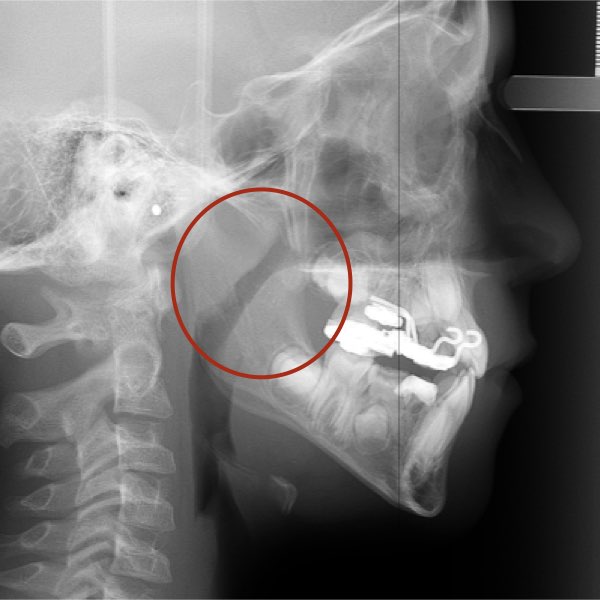

Na verdade, o diagnóstico será baseado em um primeiro momento na presença ou ausência da obstrução anatômica da via aérea em si. Nas imagens abaixo é possível ver através da telerradiografia em norma lateral a presença ou não da obstrução da via aérea superior. Sendo que diante da obstrução anatômica nossa conduta como profissionais deve ser o encaminhamento para médico do sono ou otorrino pediátrico, independente da necessidade de expansão maxilar ou protração.